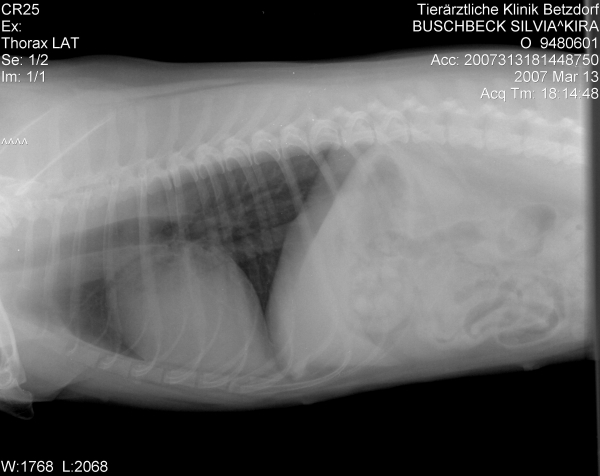

Da Kira aber inzwischen beim TA fürchterlich unter Stress steht, hat man beschlossen, zumindest schon einmal die Röntgenaufnahme des Herzens zu machen.

Die Aufnahme gefiel dem Chef nun weniger und er hat es möglich gemacht, dass Kira gestern abend dann doch noch die Ultraschalluntersuchung bekam.

Kira's Herz ist sehr vergrößert Konfus .

Zum Vergleich: ein normales Herz liegt auf ca. 2 Brustwirbeln auf, Kira's Herz beansprucht 4,5 Brustwirbel und drückt bereits die Luftröhre nach oben Geschockt

Eine Mitralklappeninsuffiziens (geringgradig), eine Pulmonalklappeninsuffizienz (ebenfalls geringgradig) und laut Diagnosebericht für meinen TA eine beginnende HCM. Hier muß ich noch einmal nachfragen, was genau damit gemeint ist.

Die Werte des Herzens sind ansonsten in Ordnung, Durchblutung, Durchflußgeschwindigkeit und Kontraktionen sind alle im Normbereich.

Sie bekommt vorerst keinerlei Medikamente fürs Herz, lediglich ein jährlicher großer CheckUp mit Herzdiagnostik wird künftig gemacht.

Die "undichten" Klappen können - müssen aber nicht - irgendwann einmal Probleme verursachen - im Augenblick tun sie es nicht.

@Christa: Ja, der Doc sagt auch, dass ein ETWAS vergrößertes Herz durchaus die Regel sei. Ihres aber ist fast doppelt so groß wie normal und zeigt zudem eine dicke Herzmuskelwand - eben die beginnende HCM. Zudem ist das Herz ja einseitig noch mal etwas vergrößert, also ungleichmäßig. Was daraus wird....man wird sehen.